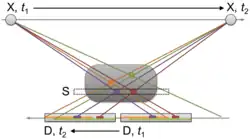

In first-generation CT scanners—such as Hounsfield's EMI Mark I design—the X-ray tube, typically operated at 120 kVp and 32 mA, emitted a narrow pencil beam aimed at a two-element detector (acquiring two 13 mm slices simultaneously), which consisted of sodium iodide (NaI) scintillators coupled to photomultiplier tubes.[13] Both the tube and the detector moved linearly across the patient at a fixed gantry angle. After each traverse, during which 160 data points (two rows of 80 measurements at 1.5 mm intervals) were collected, the system rotated by 1° around the center of the bore and repeated the process, ultimately acquiring 180 projections within five minutes. The detector required gain and offset calibration at the beginning of each linear pass.[13]

The patient's head was enclosed in a thick rubber sleeve inside a box filled with water. This "water bag" adapted the dynamic range of the X-ray signal, minimized beam hardening effects, and provided a consistent reference point for calibration of CT numbers and starting point for iterative image reconstruction.[13] The 28,800 data points collected for two slices were stored on magnetic disks.

The EMI scanner was equipped with a Data General Nova 820 minicomputer featuring 32 KB of memory and a dual-sided 2.5 MB hard drive. The reconstructed images had a matrix of 80 × 80 pixels and a dynamic range from –500 to +500, with water defined as 0. Three types of image output were available: a numerical printout of reconstructed values, a digital grayscale display with 10 intensity levels (with adjustable windowing), and a Polaroid photograph of the screen. A typical patient examination was scheduled for 60 to 120 minutes and included 8 to 12 images of 13 mm slice thickness captured via Polaroid.[13]

Devices of this generation were primarily dedicated cranial scanners, designed exclusively for imaging the head. In 1974, Robert Ledley developed the first whole-body CT scanner at Georgetown University Medical Center in Washington, D.C.—the Automatic Computerized Transverse Axial (ACTA) scanner. While conceptually similar to the EMI Mark I, the ACTA scanner offered a larger axial field of view of 48 cm and produced images with a matrix of 160 × 160 pixels.[15] Imaging body parts other than the head presented particular challenges due to motion artifacts caused by breathing and the heartbeat. To address this issue, it was necessary to significantly reduce the scan time.